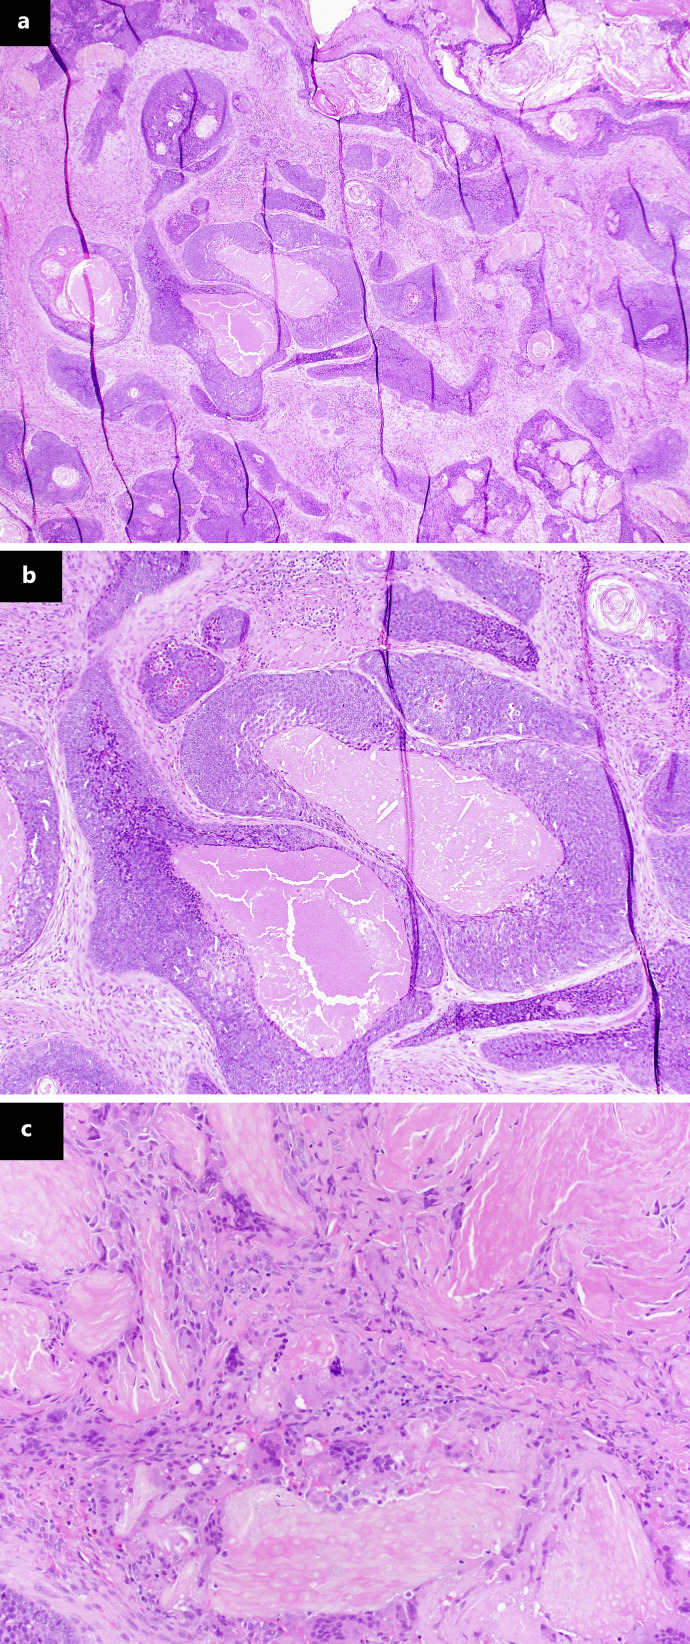

Introduction: Pilomatrix carcinomas (PMXCs) are uncommon, locally aggressive tumors with high recurrence rates, metastatic potential, and fewer than 130 cases reported in the literature. Typically, they present as an unassuming, firm, dermal swelling and therefore are frequently mistaken for more common, benign masses, leading to undertreatment which can cause local invasion and metastatic spread. Diagnosis relies on excision with pathologic analysis; however once diagnosed, there are no current recommendations to guide treatment or surveillance for recurrence or metastases.

Case presentation: Here, we present a case of one of these rare tumors. Our case describes a 1.5 × 2.5 cm firm, mobile mass at the supraorbital rim in an otherwise healthy, young patient. Prior to removal, we suspected a benign pathology; however, excision proved difficult and pathologic diagnosis was consistent with PMXC. Following discussion with tumor board, decision was made to perform Mohs micrographic surgery and staging via CT scans with regular follow-up and surveillance scans.